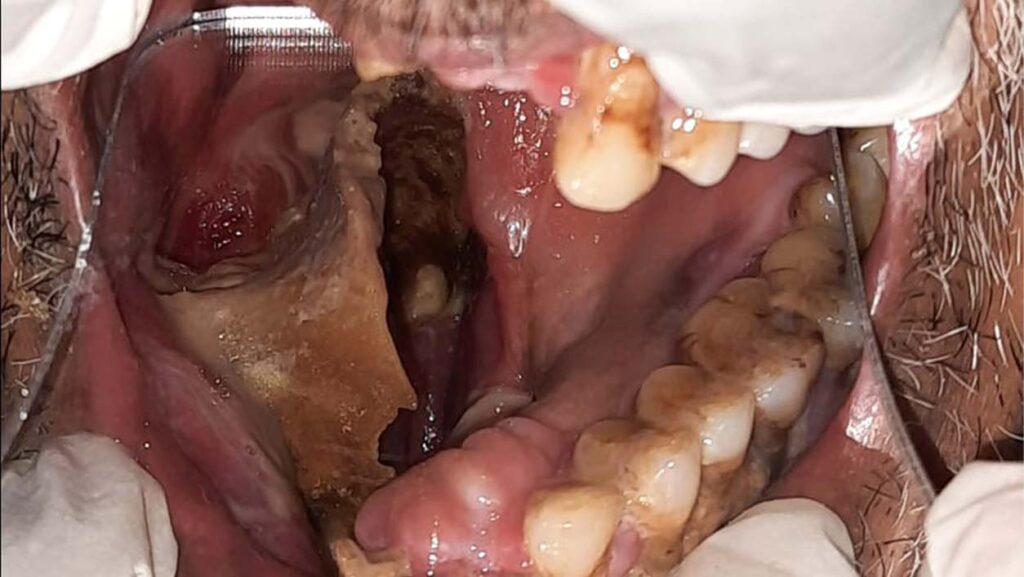

A patient suffering from black fungus | by special arrangementPatients who suffer from black fungus depend on the life saving drug Amphotericin-B. In most hospitals across the country, this drug has run out of supply. An average patient needs at least 7 vials of this antifungal drug a day for 15 to 30 days depending on the extent of the disease. Each vial costs a whopping 7000 rupees - which means - depending on the severity of the disease, a patient must spend anywhere between 12 to 15 lakh for this drug. This coupled with the hospital admission expenses and the cost of parallel drugs that are administered along with Amphotericin-B, a patient ends up spending 15 to 20 lakh for treatment. The poor who cannot afford this are succumbing to the disease and so far there has been only promises but no on-the-ground intervention from the government’s side.

A patient suffering from black fungus | by special arrangementBlack fungus takes away your dignity